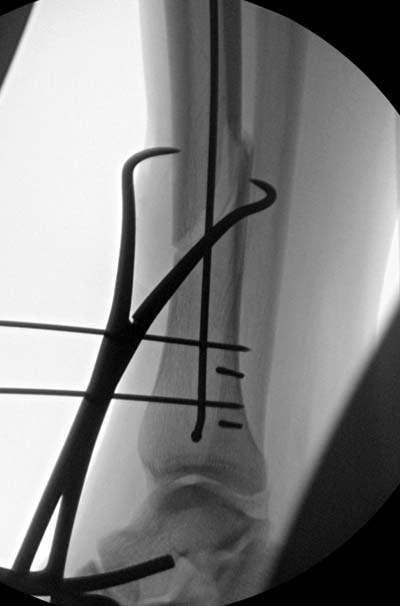

Здесь несколько снимков изолированного перелома большеберцовой с

интактной малоберцовой.  Weber clamp, блокирующие спицы и риминг в

центре канала отрепонировал перелом....